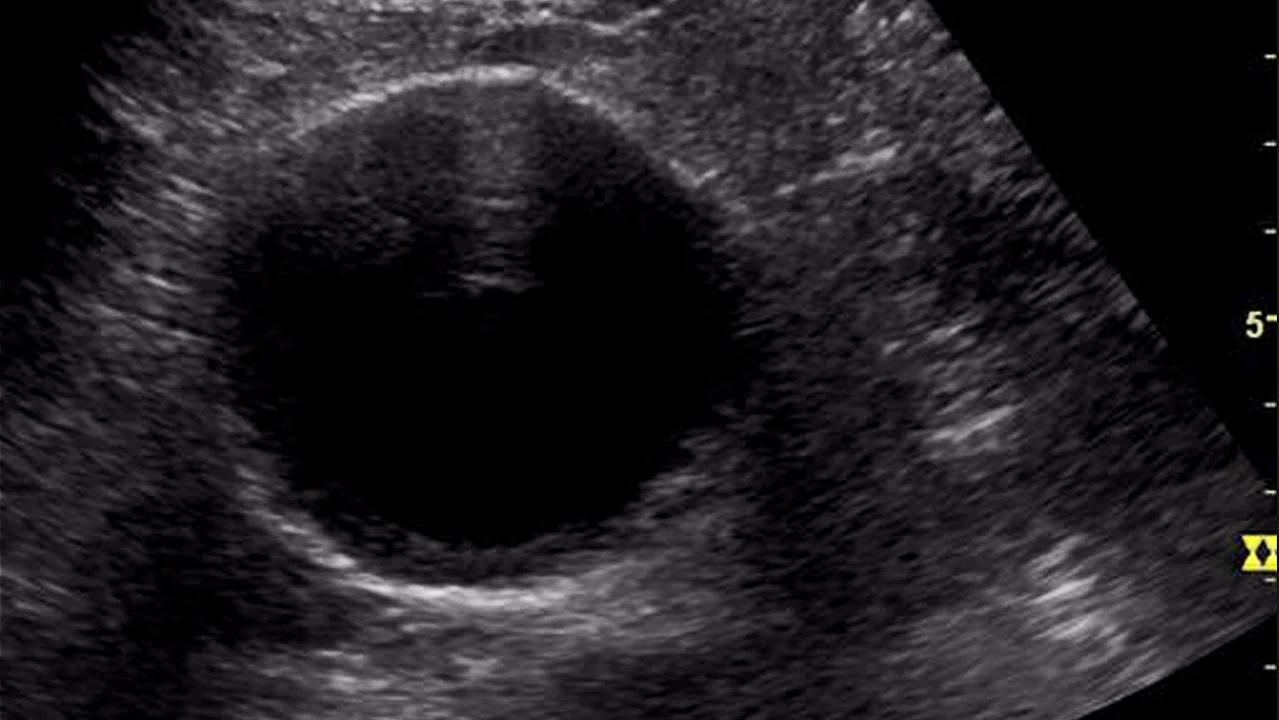

An ectopic pregnancy is when a fertilised egg implants and begins developing outside the uterus, affecting 1-in-80 pregnancies.